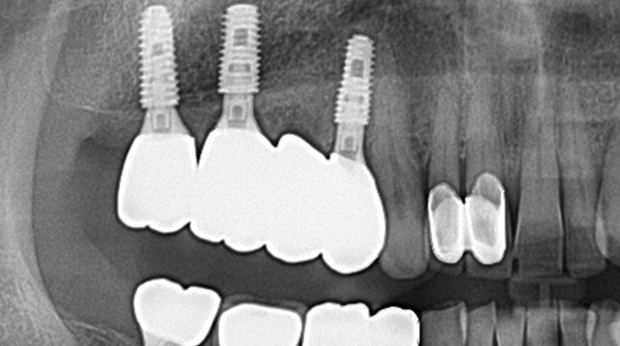

의식하진정법(수면마취)/임플란트

수술 담당 구강악안면외과 전문의

고난도 수술 진료

임플란트와 사랑니 발치는 외과적 시술로 잇몸을 절개하는 외과적 시술은

짧으면 짧을 수록 시술 후 붓기와 통증이 최소화됩니다.

치과의사 경력 14년차 구강외과 전문의가 빠르고 안전하게, 아프지 않게 수술해 드립니다.